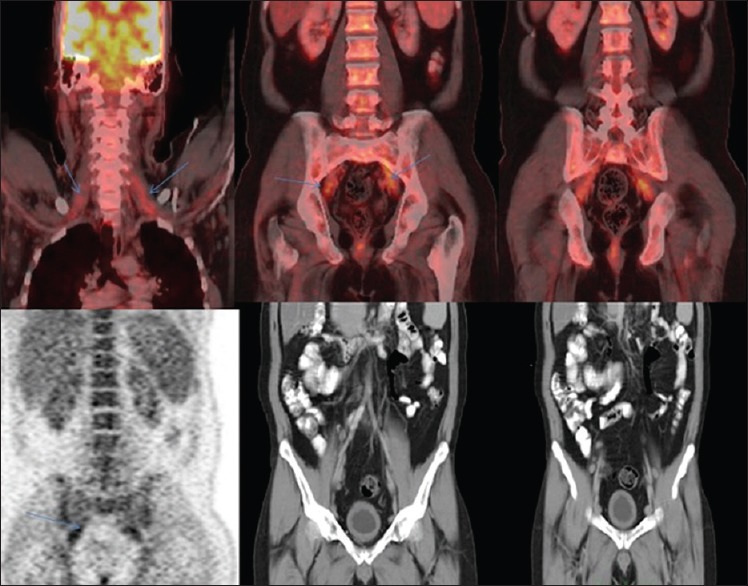

Subsequent PET-CT scan done in the same week revealed moderate-grade FDG avid lymph nodes involving bilateral external iliac regions and low-grade FDG avid lymph nodes in retroperitoneum. Non-FDG avid cervical and mediastinal lymph nodes were noted.

There was seen high-grade FDG avid uptake (maximum standardized uptake value – 12) along the lumbosacral plexus more marked on the left side and along brachial plexus on either side [Figures [Figures55 and and66].

| Figure 5:PET-CT axial images reveal intense enhancement along the lumbosacral plexus.(Left>Right), as demonstrated by tht blue arrows

| Figure 6:PET CT coronal images reveal intensely enhancing lumbar plexus and brachial pleuxs (blue arrows)